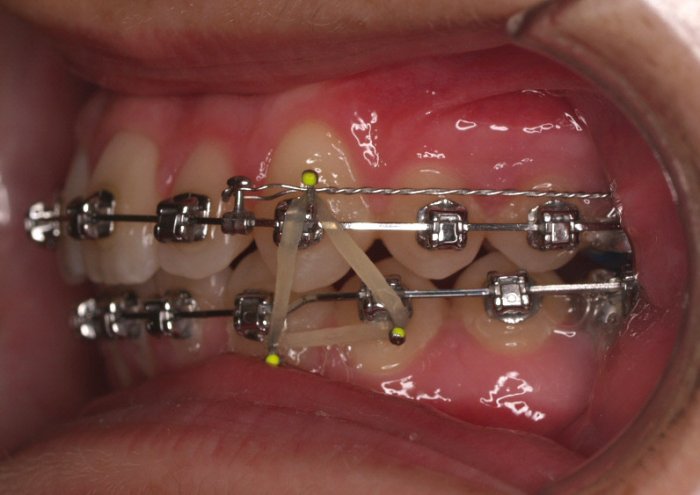

Paciente de 14 años, acude a nuestra consulta por dientes superiores proclinados hacia delante y apiñamiento. El paciente presenta una full clase 2, sobremordida y dientes inferiores proclinados. Decidimos colocarle brackets Damon y microtornillos en maxilar superior para distalizar las muelas. La duración del tratamiento fue de  24meses, y ahora lleva 1 año de contención. El paciente se pone la férula Essix superior 1noche/2 y la de abajo 1noche/semana para mantener.